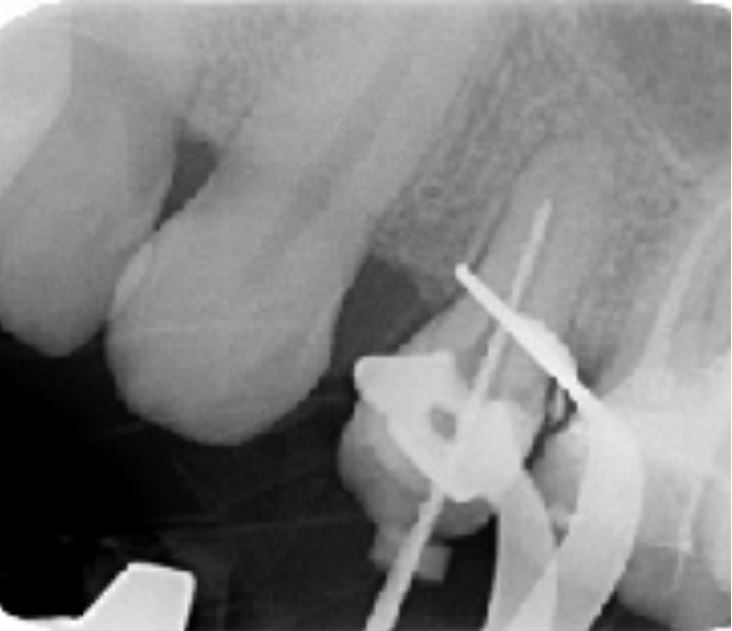

Caso clinico n. 1

Dr. Hetzel Rémy - Bourgoin Jallieu

"Trattamento di premolare con radice corta"

Anamnesi

- Dente aperto in pronto soccorso - ambiente ospedaliero

- Lima manuale K20 passata molto facilmente oltre l'apice

- Sospetto di diametro apicale non rispettato

- Prima radiografia con lima manuale K25

Radiografia intraoperatoria

- Passaggio di serie sequenziali di lime manuali

- Lunghezza di lavoro determinata con lima K20

- Lunghezza di lavoro fissata a 17,5 mm

- Lima apicale maestra di 30/100

- Sagomatura con la sequenza Fanta ROTARY fino alla lima 30/04%